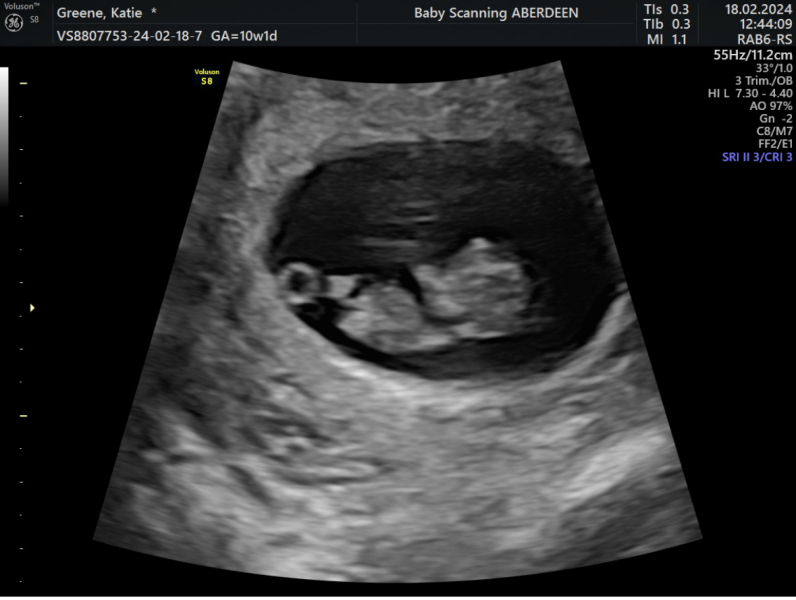

Went for a private scan this morning, twin has almost been fully reabsorbed and remaining baby has sped up some growing and is measuring 9 weeks exactly. Got to see it dancing around 💕 very relieved after some heavy bleeding this week!

MrsB2019x · 18/02/2024 15:02

Gorgeous scans ladies 😍😍😍

Oh all the scans are fab!! I also went for one on Saturday morning and baby measuring two days over so now 9+2 so feeling good and reassured 🥰

Amazing scans girls! I can’t believe we’re coming up to the 12 week mark already!